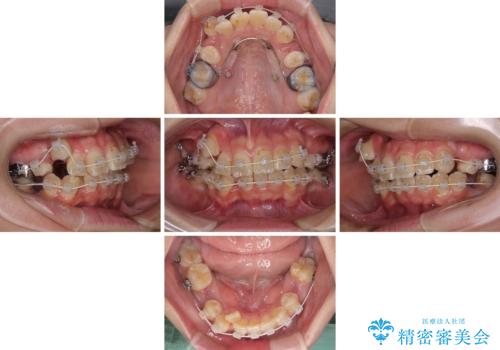

- 審美装置

- 4年4ヶ月

- 30回以上

重度叢生のため、大臼歯をしっかりと咬合させるために、下顎は左右第二小臼歯を、上顎は前歯部の叢生を解消するために左右第一小臼歯を抜歯し、口元の突出感を改善するために、上顎大臼歯が前方に移動しないようにするために、補助装置による架強固定を行うこととしました。

叢生は思ったよりも早期に改善されましたが、舌の突出癖による上下前歯の非接触が全く改善されず、2年間ほど治療期間が延びる結果となってしまいました。